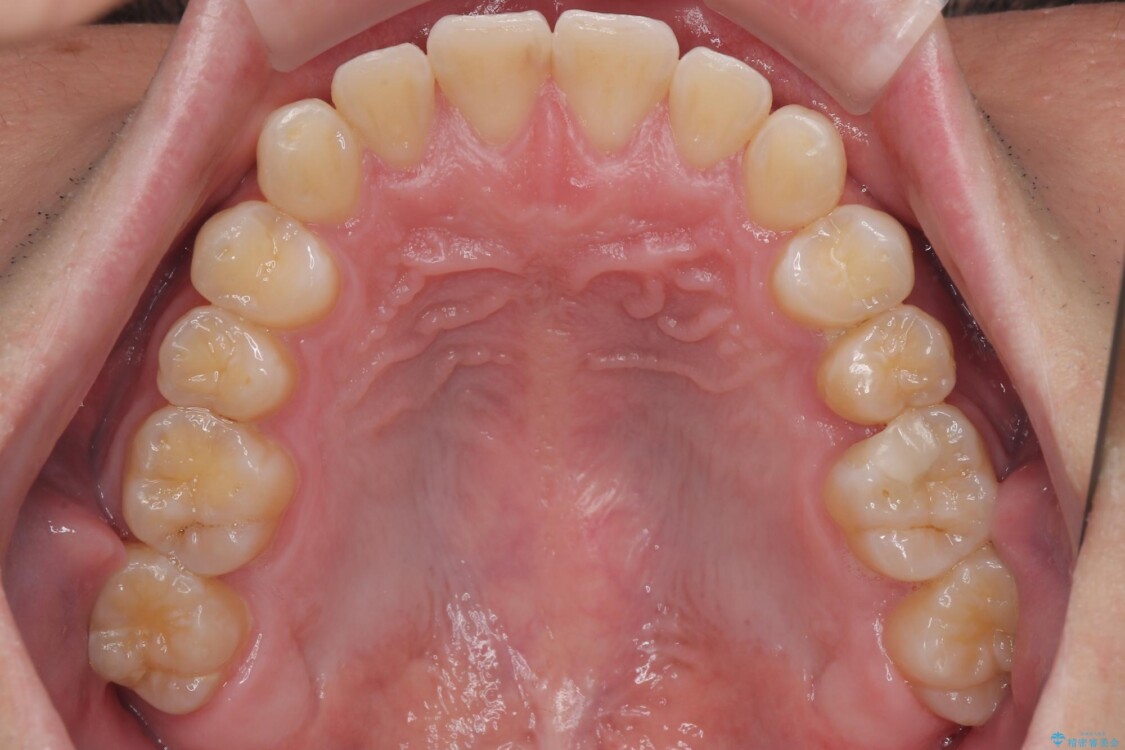

主訴:前歯のデコボコと奥歯のかみ合わせを治したい 今回ご紹介するのは、「前歯のガタガタ(叢生)」と「奥歯のかみ合わせ(シザーズバイト)」にお悩みでご来院された患者様の症例です。 患者様は、 ・歯並びをできるだけ早く改善したい ・費用を抑えた矯正治療 というご要望をお持ちでした。

・上顎左右の第二大臼歯が頬側へ転移し、シザーズバイト(scissors bite)の状態

・上顎左側第二小臼歯が90度捻転しており、噛み合わせに影響

治療前

• 前歯のガタガタ・奥歯のかみ合わせ(シザーズバイト)を改善|1年半で完了したメタルブラケット矯正 治療前画像